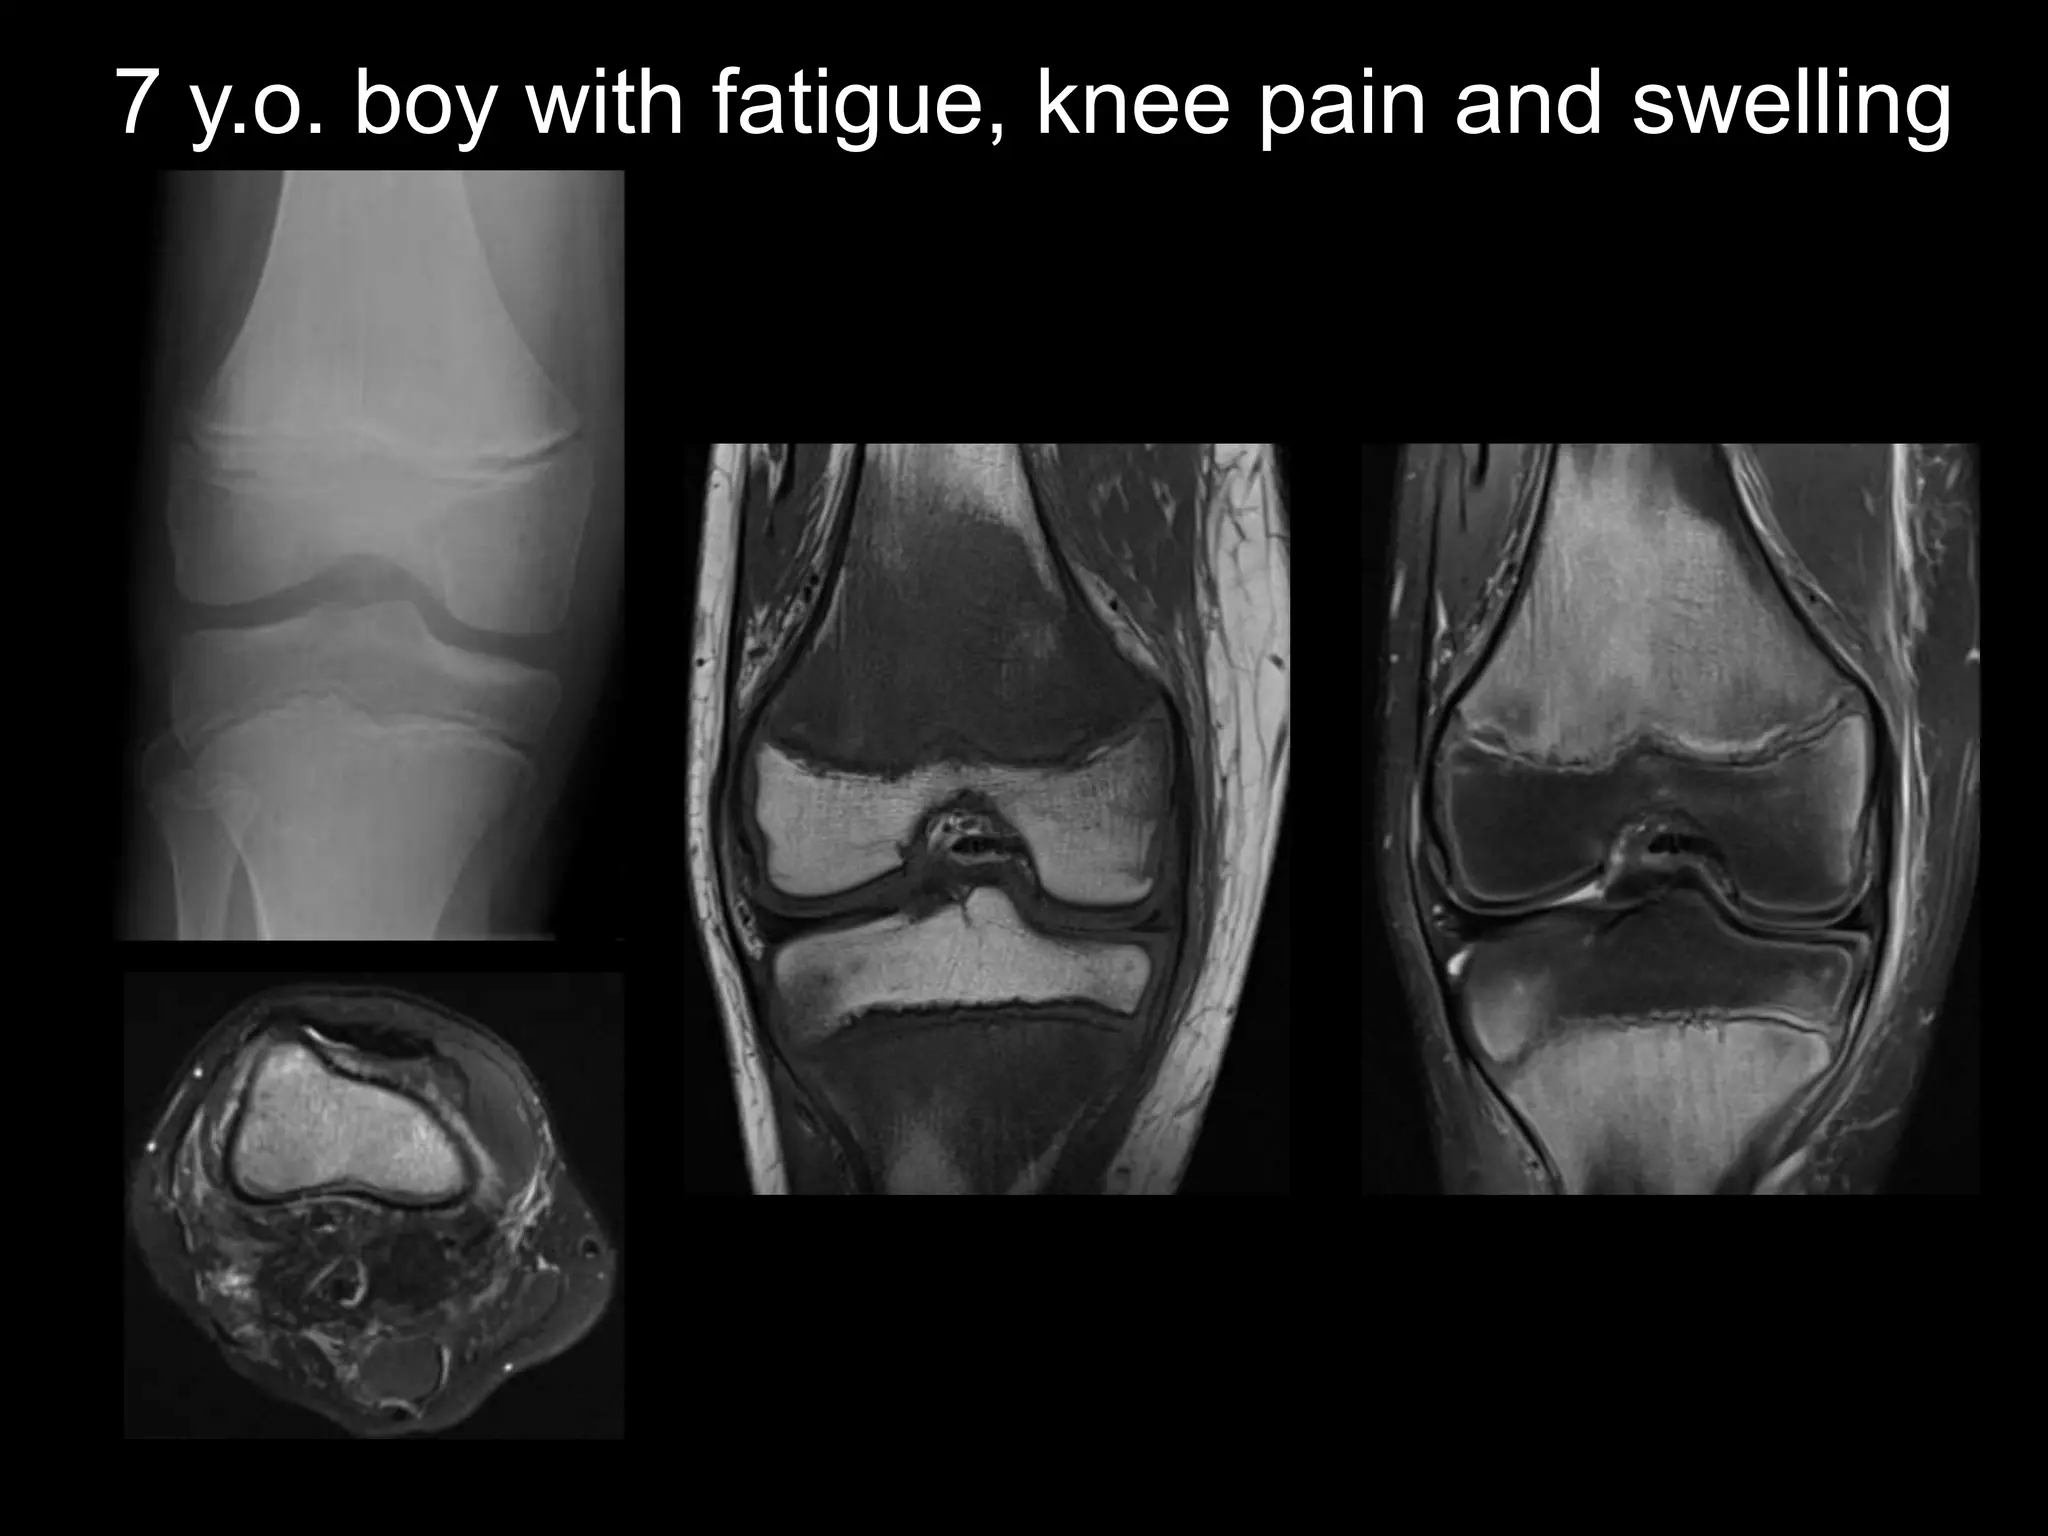

7 y.o. boy with fatigue, knee pain and swelling

• Xray findings (late)

– Prominent ZPC (white lines of

Frankel)

– Subjacent lucent bands (scurvy

lines)

– Physeal widening

– Epiphyseal (Pelkan) spurs

– Metaphyseal fractures

• MR findings are non-specific

– Metaphyseal marrow changes

– Periosseous soft tissue edema

– Subperiosteal fluid/hematoma

(late)

Scurvy

• Intramedullary and subperiosteal

hemorrhage

• Gelatinous transformation of marrow

• Our patient

– Marrow bx – fibrosis, hemorrhage

– Restricted diet: chicken

nuggets, water, packaged cookies

– Further eval: autism spectrum diagnosis